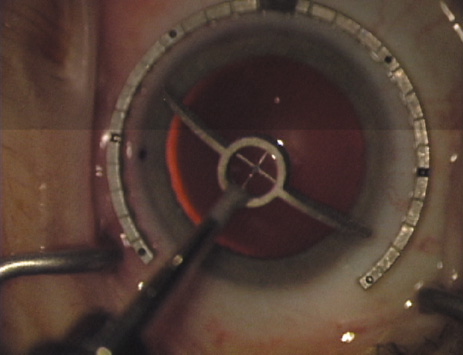

Another less common method of creating peripheral relaxing incisions is to use a device such as the Terry/Schanzlin Astigmatome (Oasis Medical), which circumvents the need to make a “free-hand” incision. This trephine-like device has been designed to create consistent and symmetric peripheral arcuate corneal relaxing incisions. It uses a vacuum speculum that mates with various reusable templates that are selected based upon the amount of astigmatic correction that is desired. The incision is created by simply rotating a disposable steel blade unit that fits inside of the template (Fig. 7).

Fig. 7. The Terry/Schanzlin Astigmatome.